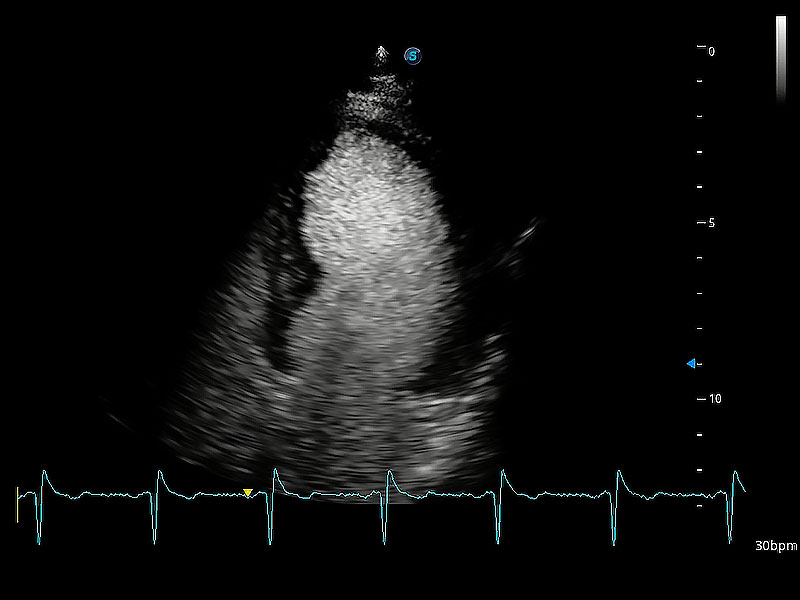

(貓)二尖瓣M型

(犬)二腔心血流